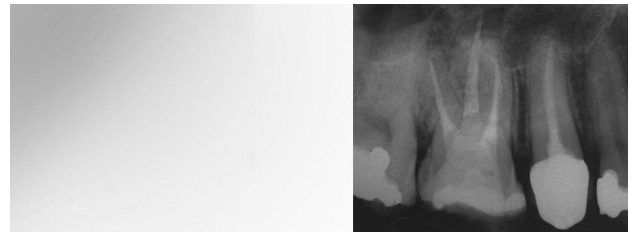

WURZELKANALBEHANDLUNG (ENDODONTIE)

Bei einer Wurzelkanalbehandlung wird das Gefäß-Nervenbündel (Pulpa) des Zahnes vollständig entfernt. Die Wurzelkanäle werden durch Spüllösungen desinfiziert und mit speziellen Wurzelkanalinstrumenten aufbereitet. Die Anzahl der Wurzelkanäle ist je nach Zahn unterschiedlich.

Die Wurzelkanalbehandlung findet ihren Abschluss mit dem Einbringen einer den Wurzelkanal vollständig ausfüllenden, bakteriendichten Wurzelfüllung.